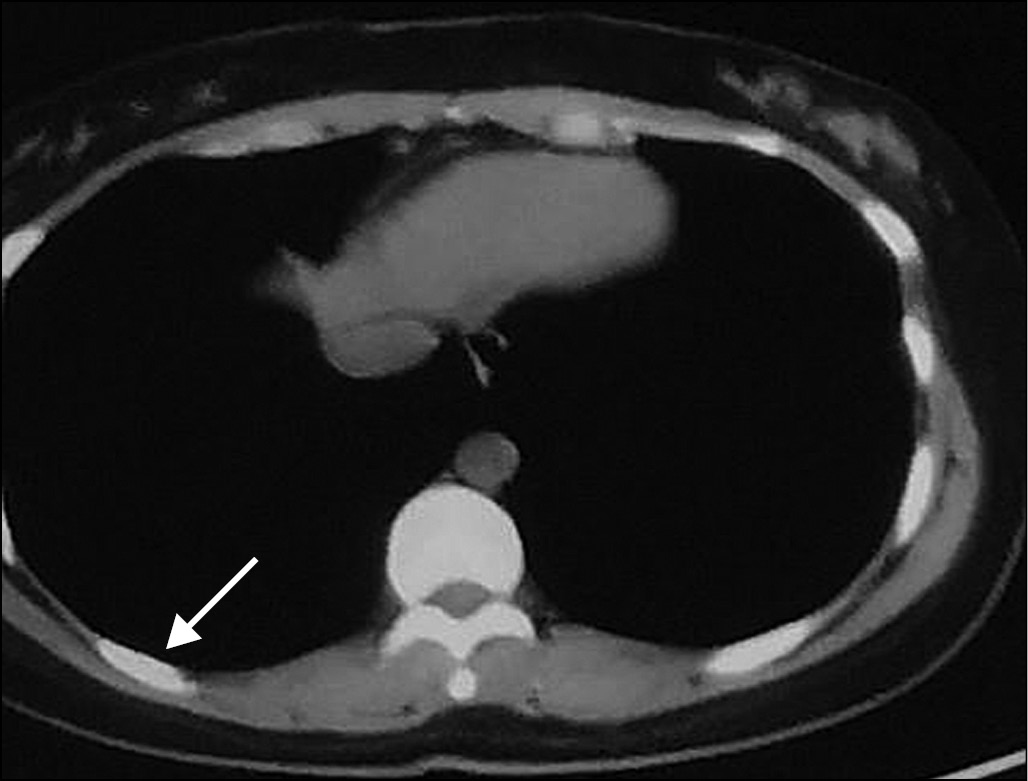

Компьютерная томография. Всего за время исследования получено 115 результатов КТ лёгких. По первым КТ-изображениям, выполненным до лечения, у 45,3% пациентов выявлен симптом «матового стекла», у 65,6% — бронхит, у 21,9% — фиброз, у 14,1% — кальциноз, у 12,5% — узловые образования. У 2 пациентов обнаружено утолщение плевры, у 3 — каверна лёгкого, у 2 — застарелый туберкулёз лёгких. Согласно результатам, между двумя возрастными группами не найдено статистически значимого различия по большей части поражений (p > 0,05); табл. 1, рис. 1–3.

Рис. 3. Утолщение плевры справа (стрелка).